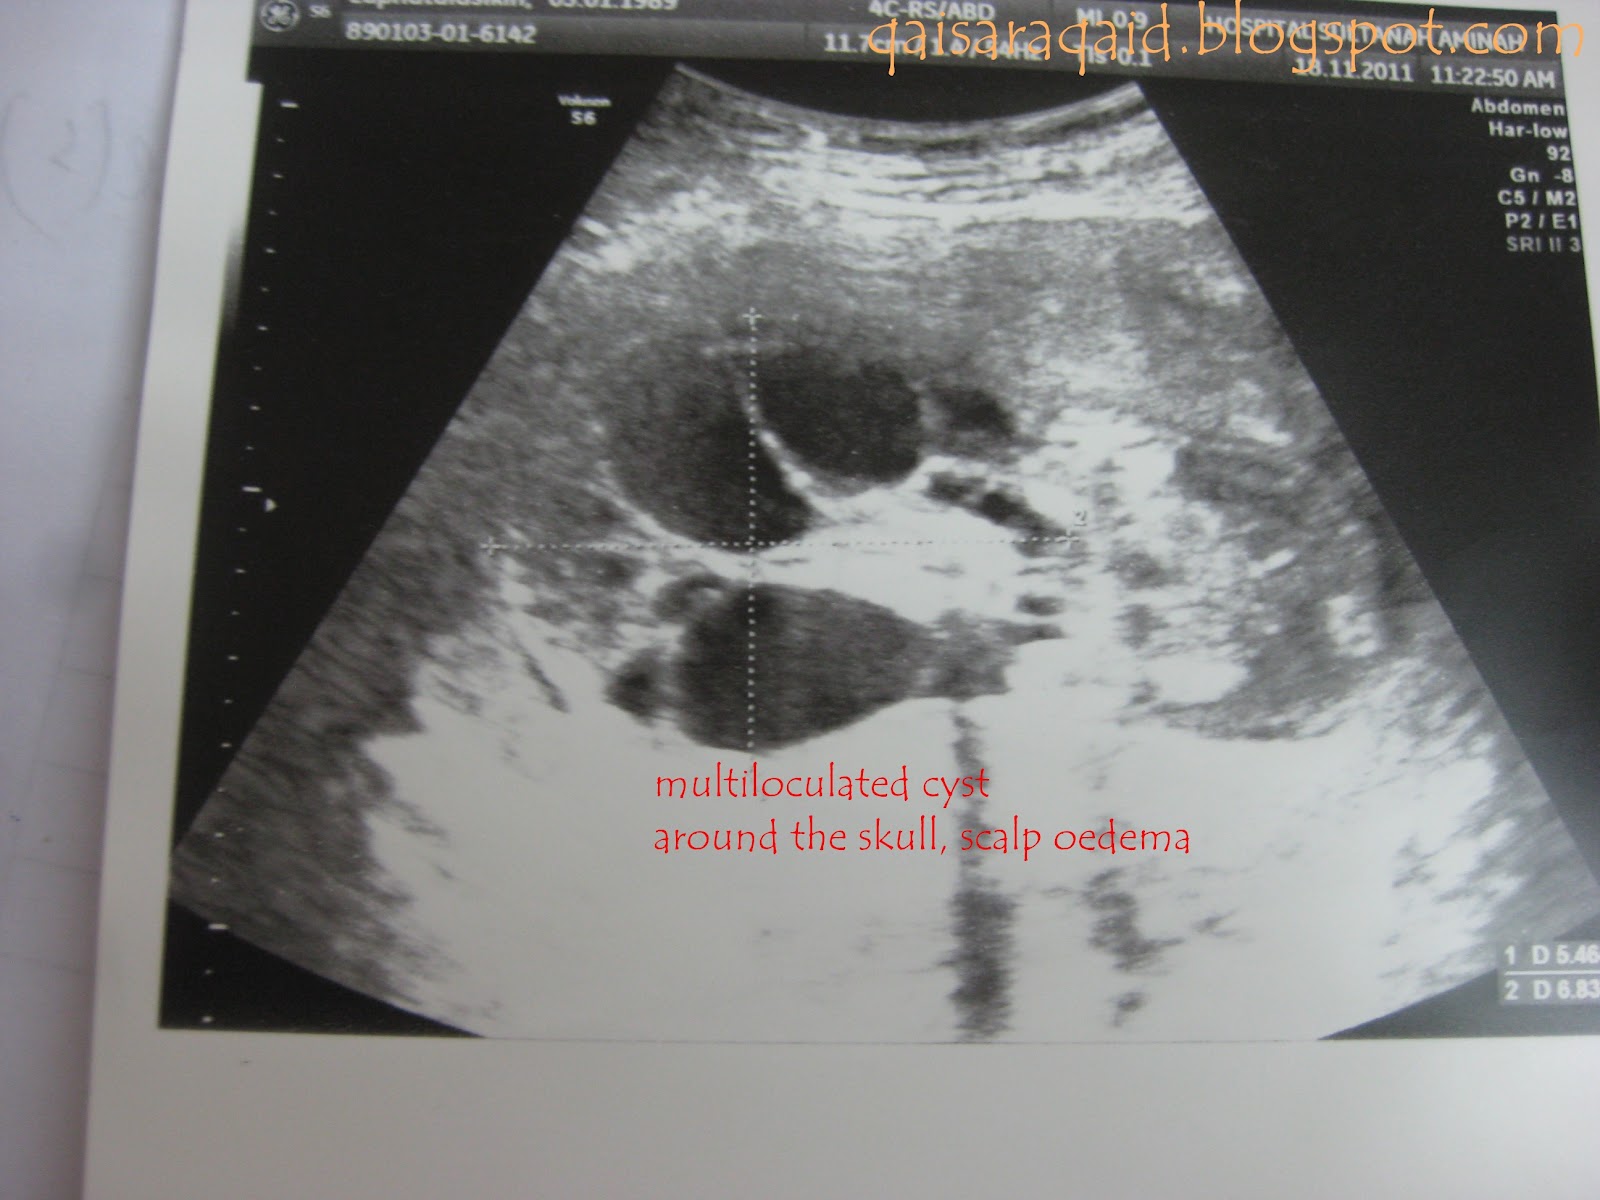

Sonograms demonstrating cystic hygroma and fetal hydrops.

What is the striking lesion seen in the scan? In 10% of cases the fetal karyotype is normal, there are no other obvious defects and the hygromas resolve during pregnancy. Cystic lesion appears to have few thin septations. Cystic hygroma with hydrops fetalis.

Minor hydrops is common, particularly in premature infants. The transverse sonogram in a shows a cystic hygroma with a midline septum. I had a cvs, which after 2 insertions didn't work so had an. Too much fluid within the baby's body.